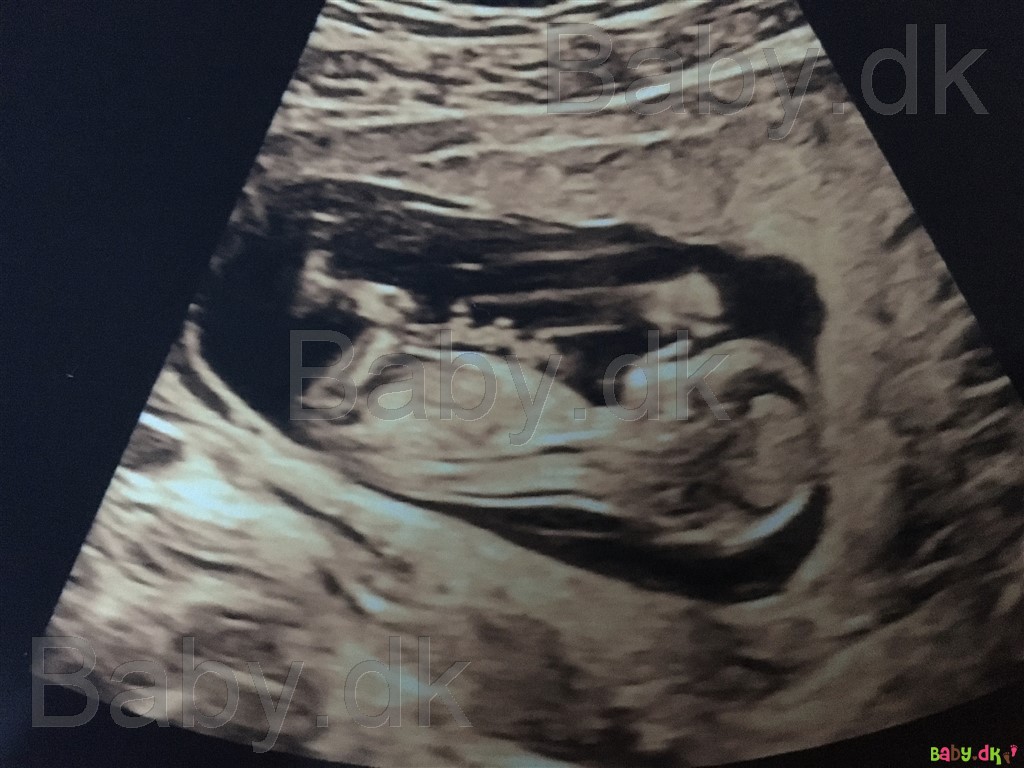

Vi har lige været til nakkefoldsscanning idag, hvor alt så godt ud. Men jeg er både spændt og utålmodig på kønsscanningen om 2 uger og tænkte der sikkert var nogle garvede der ville komme med et bud på om det er en dreng eller pige vi venter os?

Vi har selv haft fornemmelsen af at det var en pige, men jeg er kommet i tvivl og synes at kunne ane noget på billedet?

Jeg er 12+4. Håber nogle vil give et bud, ønsker alle en god dag